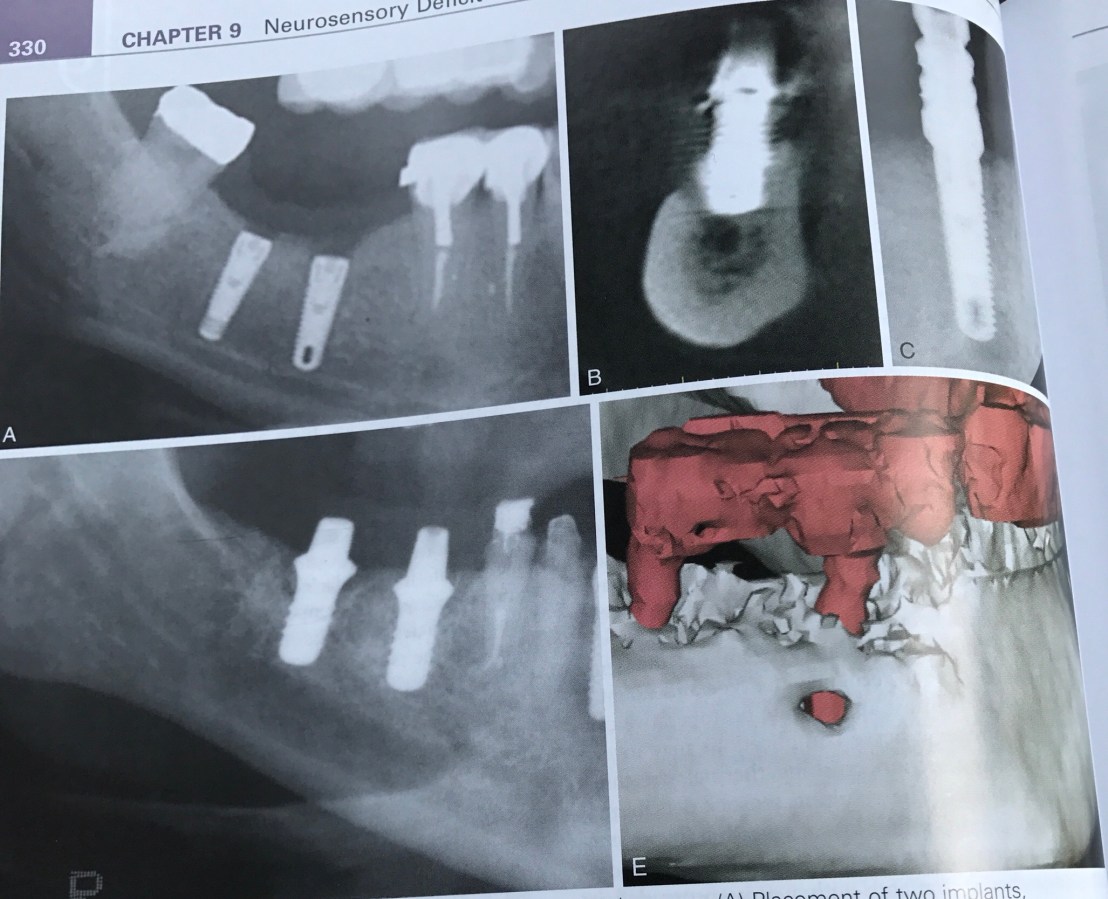

บทที่ 9 อาการชาที่เกิดจาก Implant

จุดประสงค์ของบทนี้คือ การป้องกันอาการชาครับ

Film แสดงการวางตำแหน่ง Implant ที่ลึก (เทียบระดับ CEJ) และปลายที่รบกวน Mand canal

ถ้ามอง Cross section view ในรูป B รูเปิดที่เห็นด้าน buccal นั่นคือ Mental foramen ครับ

รูป E ภาพ CBCT แสดงการยืนยันชัดเจน